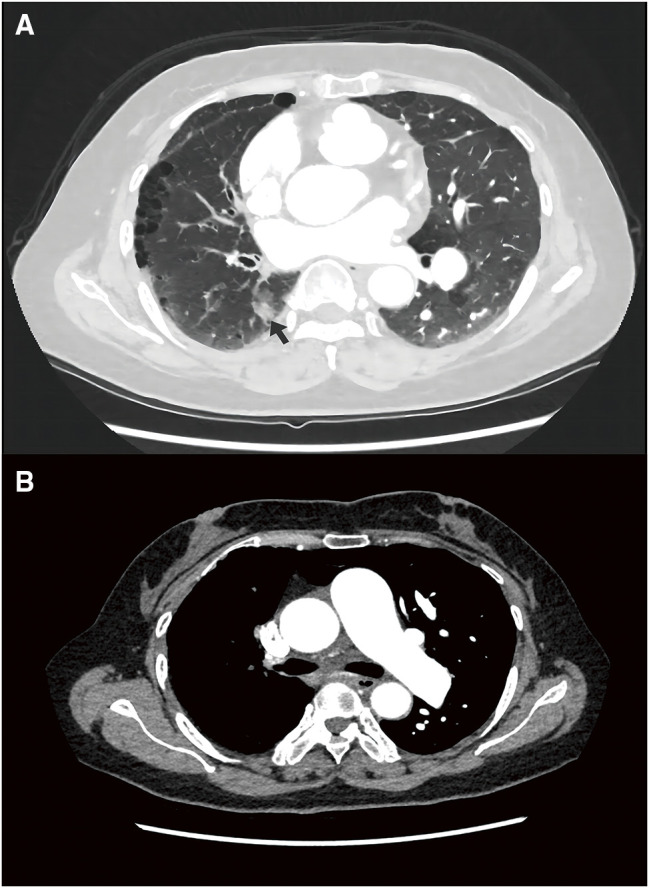

单侧肺动脉缺失(UAPA)是一种不常见的先天性畸形。在较罕见的情况中,UAPA 合并肺癌的病例此前已有 13 例报道;然而,关于手术方法和注意事项仍存在争议。在此,我们介绍了一例 56 岁女性患者的病例研究,她在一次常规体检中偶然被诊断为右肺下叶结节,随后在术前评估中发现右肺动脉缺失。患者接受了右肺下叶楔形切除术。术后病理证实为浸润性腺癌(pT1N0M0)。我们对有关这些患者的现有文献进行了叙述性回顾,并讨论了最佳手术治疗策略。

Unilateral absence of a pulmonary artery (UAPA) is an uncommon congenital anomaly. Among the rarer conditions, UAPA with lung cancer has been previously reported in 13 cases; however, there remains controversy regarding the surgical approach and precautions. Herein, we present a case study of a 56-year-old female patient who was incidentally diagnosed with a nodule in the right lower lobe of the lung during a routine physical examination and subsequently found to have an absent right pulmonary artery upon preoperative evaluation. A wedge resection of the right lower lobe was performed as treatment. Postoperative pathology confirmed invasive adenocarcinoma (pT1N0M0). We provide a narrative review of existing literature on these patients and discuss optimal surgical management strategies.